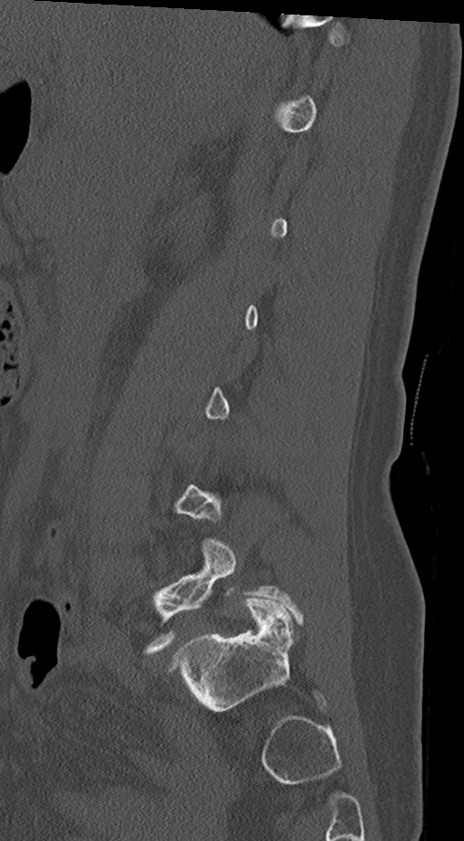

【整形】TIPS症例4 腰椎CT(矢状断像)

腰椎CT

冠状断像